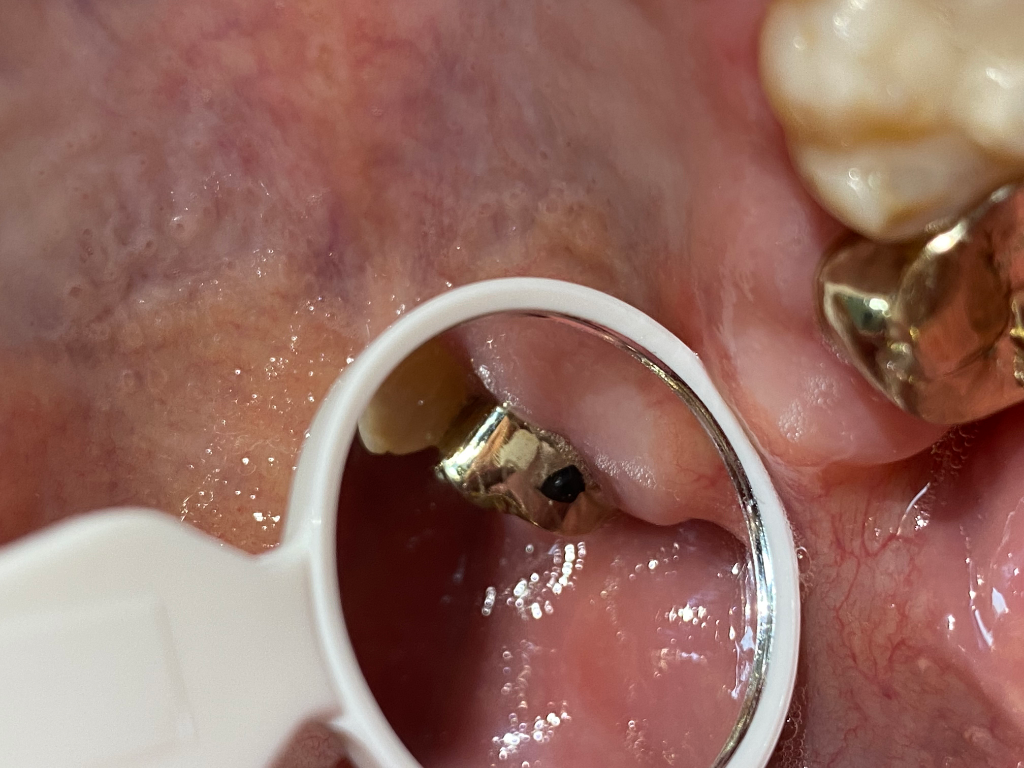

사진만으로는 정확한 판단이 어렵지만 크라운 자체가 불량일 가능성이 있어 보입니다. 물론 말씀드리기 상당히 조심스러우며 해당 치과 방문 후 관련된 부위에 대해 문의를 해보는 것이 필요해보입니다. 따라서 치과 방문을 권해드립니다.

직접 확인하지 않아

확답은 힘듭니다만,

크라운 겉면에 이물질이 묻은것이거나,

크라운이 뚫린 경우일 수도 있어보입니다.

치과에 가보셔야될것같습니다. 음식물이 묻은게 아니라면 일반적은 금니는 저렇게 검정색이 잇진 않습니다.

금니 크라운은 합금이기 때문에

금 함량에 따라 변색이 있을수 있습니다.